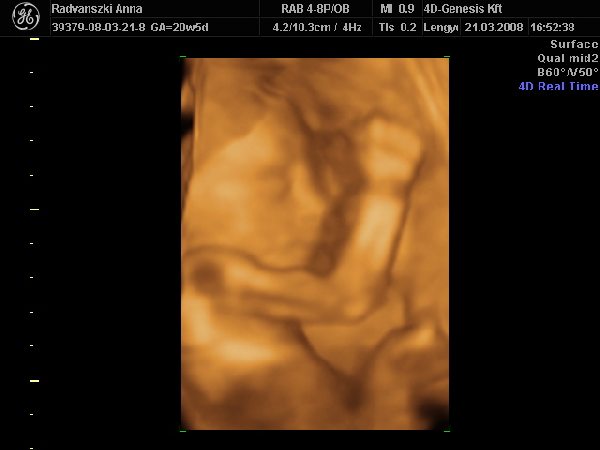

Még múlt 7pénteken elmentünk végül is 4D-re. Nagy élmény volt, bár aznap reggelre éreztem, hogy fejenállásba ment át a picur, mert felül a köldökömnél rugdosott. Így aztán az UH-n elég sokat kellett vadászni, hogy jól látszodjon a kis pofija, de a hölgy nagyon türelmes volt. Úgy 50percet vizsgált, közben csokiztunk is egy kicsit, hátha azzal nagyobb mozgásra késztetjük a pöttömöt. Hát sikerült is, mert megpróbálkozott egy bukfenccel. Szegényke nagyon taposott a kis lábaival :D , a fejét meg tisztára maga alá görbítette, de a talpa mindig megcsúszott a méhfalon, így nem sikerült neki a produkció. De azért sikerült egy kicsit kijjebb kecmeregni e magát, így aztán néhány viszonylag jól látható képet is tudtak róla készíteni.

Megnézték mindenét, mindene nagyon szép és rendben van, makk egészségesnek tűnik. :lol:

És m egint azt mondták, hogy kislány. Mondjuk a beterpesztés elmaradt, de nézte a néni 2d-vel, 3D-vel is, és azt mondta, hogy nincs a lába között semmi :lol:

Íme egy pár kép a kiscsajszinkról :D :